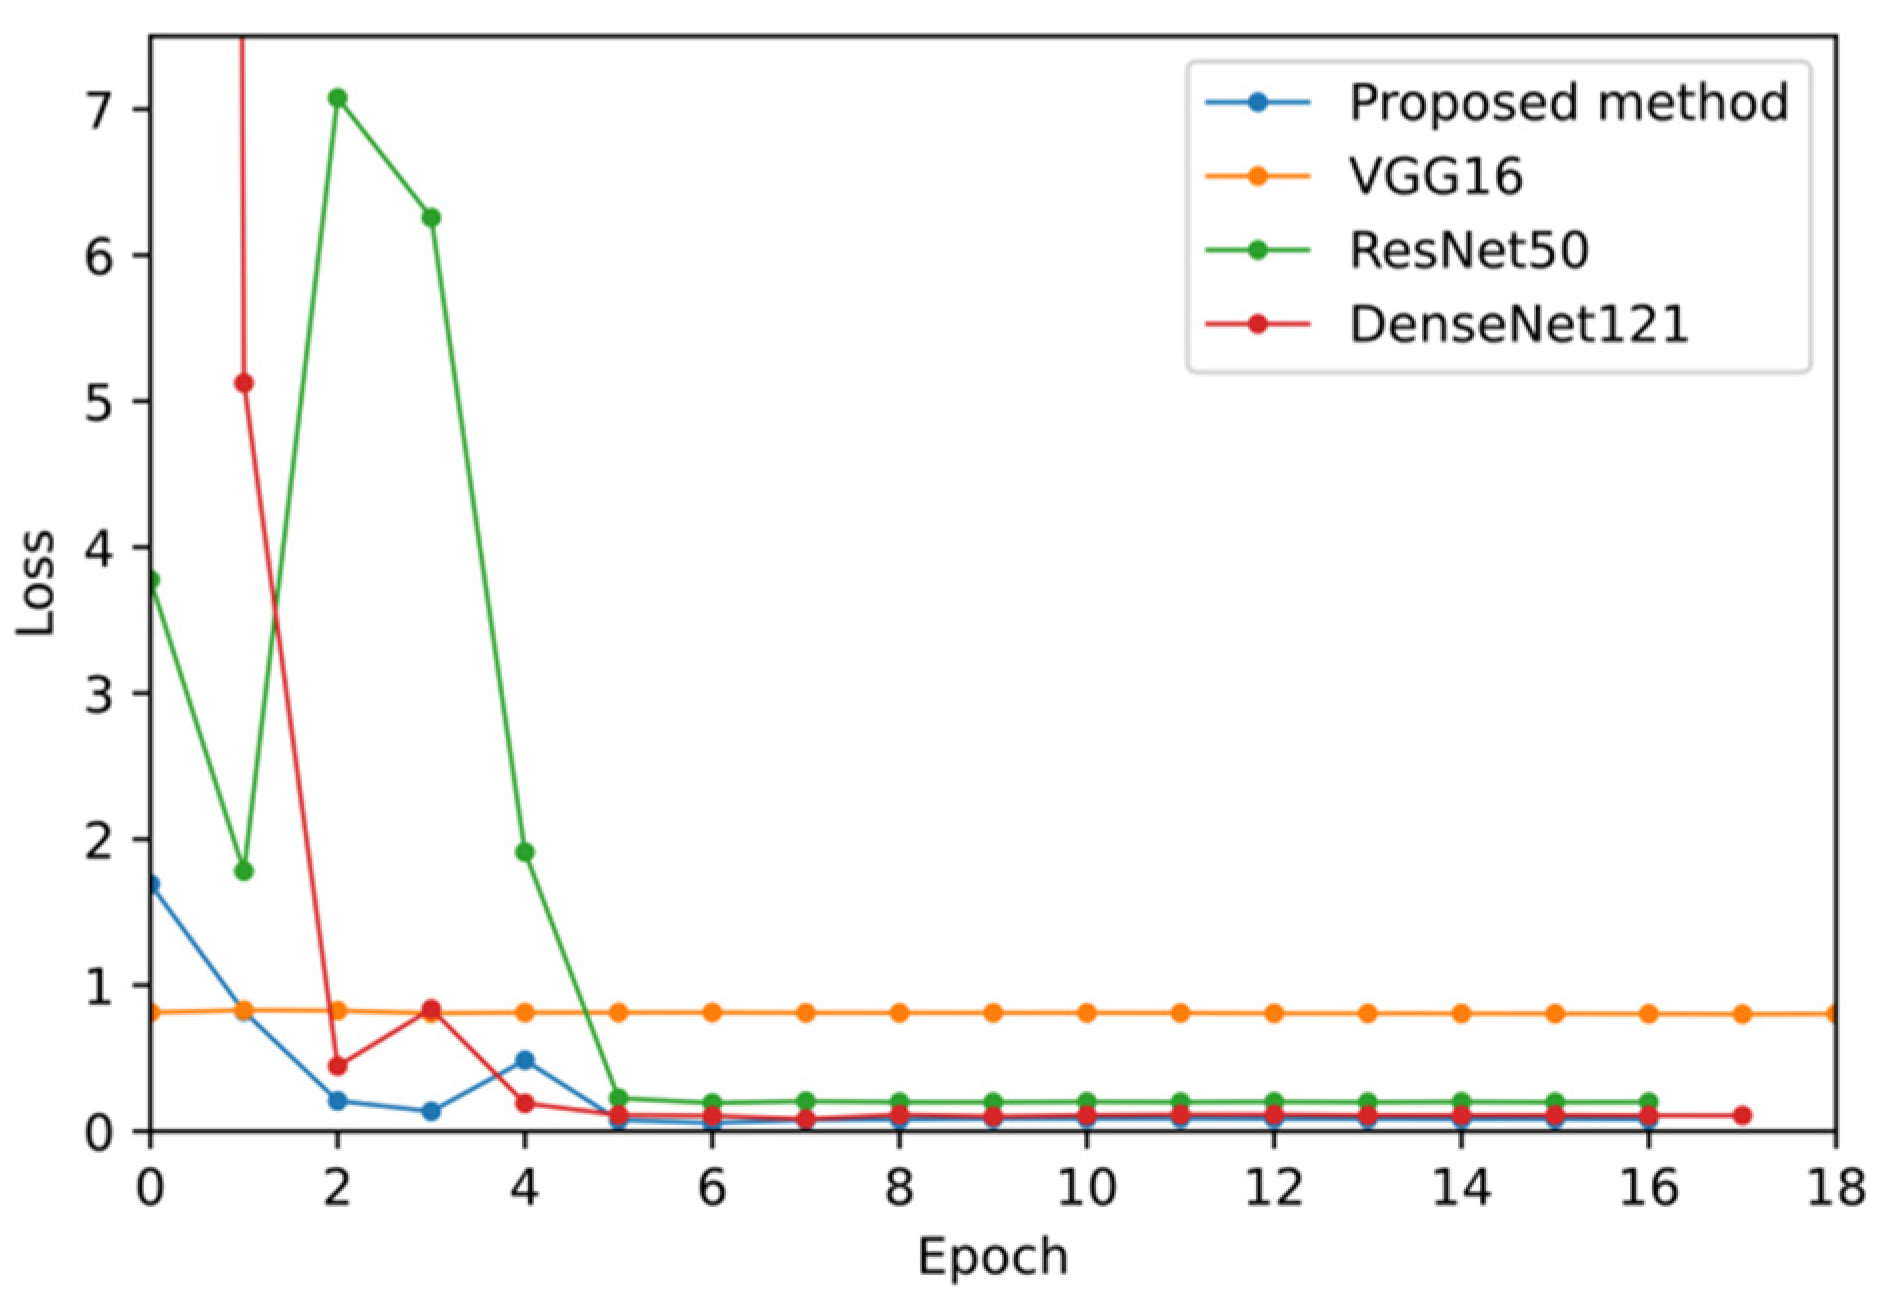

5.2. Validation Set Results

| Model | Best Epoch | Validation Loss | Average Training Time (Epoch) | Average Training Time (Example) | Convergence Time (Best Model) | Training Total Time |

|---|---|---|---|---|---|---|

| VGG16 | 34 | 0.79751 | 80 s | 0.0181 s | 2720 s | 3520 s |

| ResNet50 | 7 | 0.19316 | 78 s | 0.0177 s | 546 s | 1248 s |

| DenseNet121 | 8 | 0.08312 | 74 s | 0.0168 s | 592 s | 1258 s |

| Proposed method | 6 | 0.05619 | 100 s | 0.0226 s | 700 s | 1600 s |